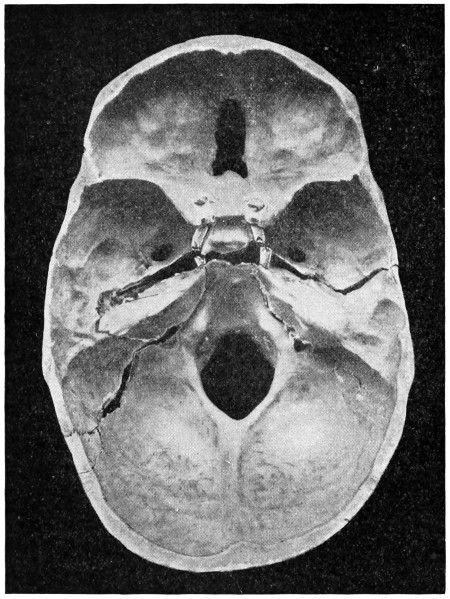

50 A and B. The inner aspect of the skull and the same seen on transillumination 137

51. To illustrate compression of the brain as produced by an extra-dural hæmorrhage from the middle meningeal artery[x] 141

52 A and B. The operative treatment of middle meningeal hæmorrhage 144, 145